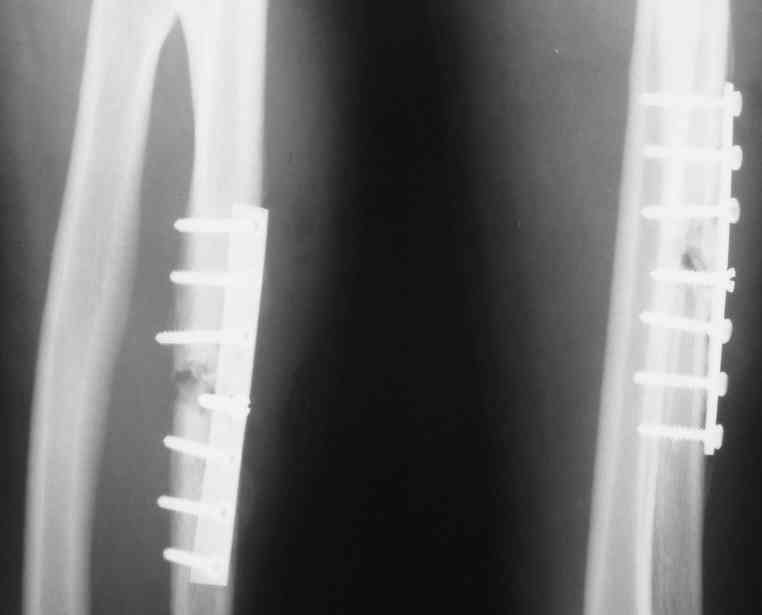

Здравствуйте уважаемые коллеги! На лечение 08.10.07 поступил больной Т. 25 лет.Травму получил 2,5 мес назад:"парирующий" оскольчатый перелом средней трети диафиза левой локтевой кости со смещением.

07.08.07 выполнена открытая репозиция,остеосинтез локтевой кости пластинкой.Послеоперационный период осложнился нагноением п/о раны. Выполнено дренирование п/о раны с установкой промывающего дренажа,антибиотикотерапия.Явления воспаления купированы.В настоящее время в ср/3 левого предплечья,в проекции п/о рубца, имеется рана,размерами 2,0х0,8 см со скудным гнойным отделяемым,умеренный отёк мягких тканей.Данные R-графии через 2 месяца после операции представлены. Хотелось бы узнать ваше мнение о тактике дальнейшего лечения: Целесообразно ли удаление фиксатора в данной ситуации? И если да,то альтернативный способ фиксации отломков? Объём оперативного вмешательства? Способ замещения дефекта локтевой кости? Заранее признателен,с уважением В.